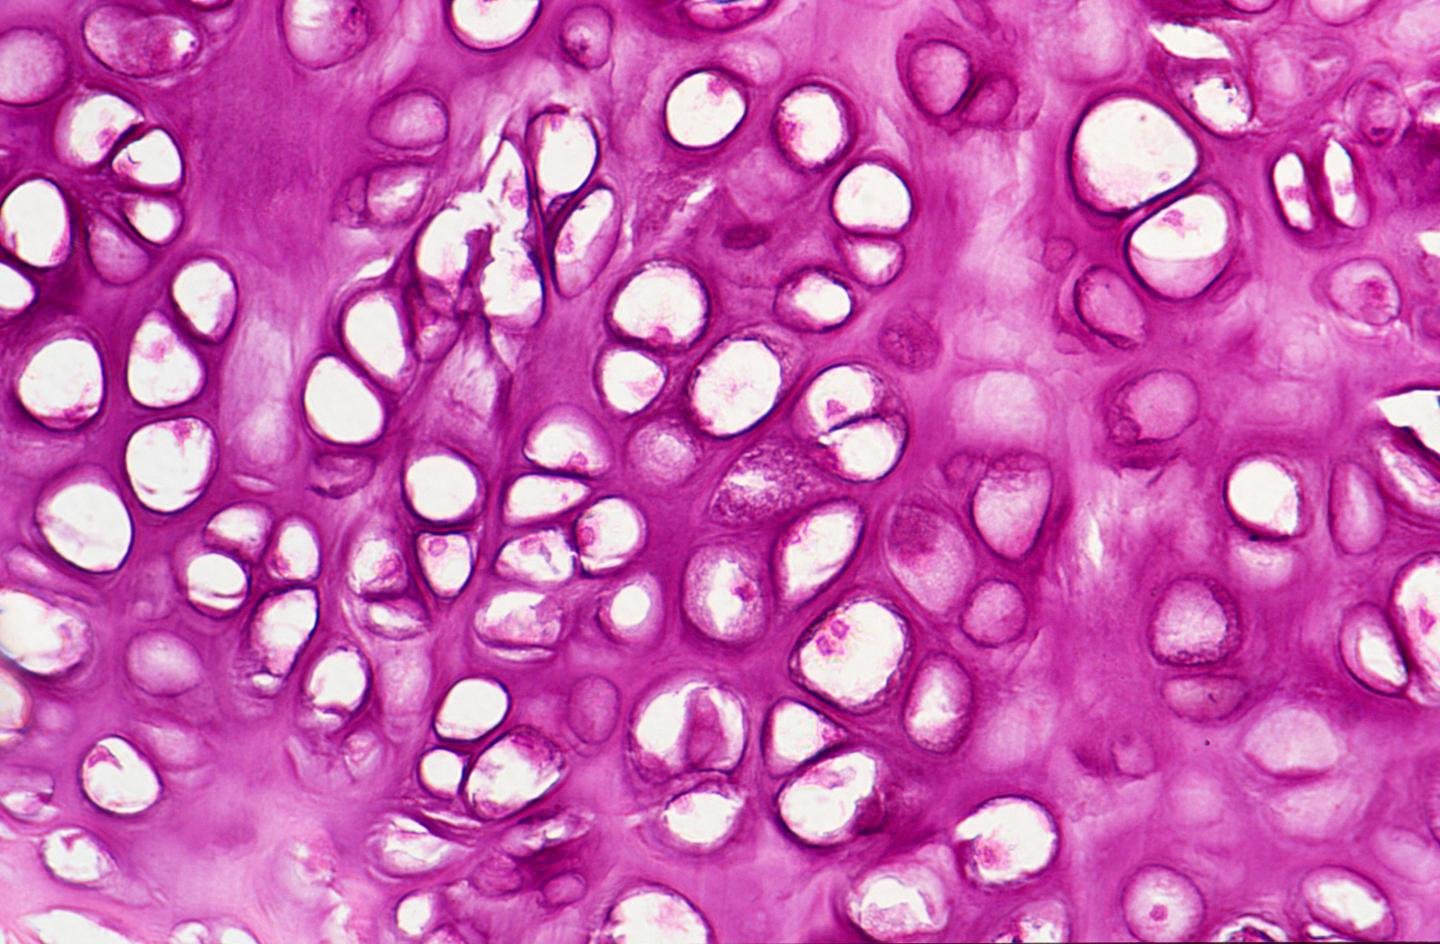

Хрящевая Ткань Фото

Хрящевая Ткань Фото 109 фото